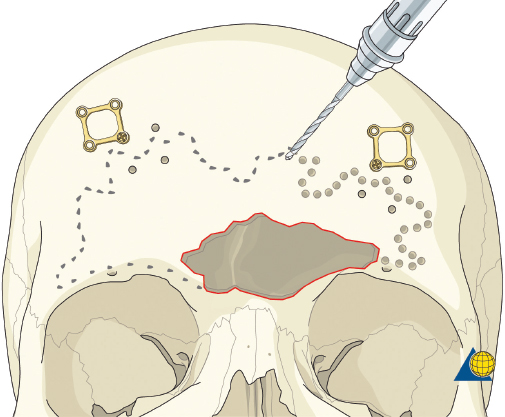

More severe injuries involving the anterior and/or posterior table(s) may require sinus obliteration. The exposure has been described above (open reduction and internal fixation). It is important to maintain a viable pericranial flap that can be used for dural repair if necessary. After complete exposure of the frontal bone (and orbital rims as necessary), all anterior table bone fragments should be carefully removed and kept moist on a side table. It is helpful to maintain the orientation of the fragments with a drawing to assist with re-orientation during the final repair ( Fig. 63.35 ). It is often necessary to complete the frontal sinusotomy, and remove any remaining anterior table bone to visualize the entire sinus. Intraoperative navigation can be useful to define the margins of the sinus. Alternatively, one tine of a bipolar cautery can be placed through a defect in the anterior table and walked around the periphery of the sinus. The outer tine is used to mark the outline of the sinus externally ( Fig. 63.36 ). Transillumination can also be used to outline the sinus. A light source is placed within the sinus, illuminating the periphery, which is then marked in a similar fashion ( Fig. 63.37 ). After the limits of the sinus have been marked, several microplates are pre-applied across the proposed osteotomy sites ( Fig. 63.38 ), maintaining the precise location of the bone flap at the completion of the procedure. The plate is rotated superiorly and the osteotomy is performed ( Fig. 63.39 ). The author prefers a high-speed Midas Rex drill (Medtronic, Inc.) and a B-1 bit. The same tool can be used to make perforations along the periphery of the sinus ( Fig. 63.40 ), and complete the osteotomy by joining the perforations with side cutting capabilities ( Fig. 63.41 ). The osteotomy line should be angled toward the sinus cavity to avoid intracranial penetration ( Fig. 63.42 ). The orbit rims and glabella can be osteotomized with either the drill or osteotomes depending on the degree of preexisting comminution; however, the surgeon must protect the supratrochlear and supraorbital neurovascular pedicles. Finally, an osteotome is inserted through the superior saw kerf and used to break down any intersinus septations, and bone flap is removed ( Fig. 63.43 ).

Type II fractures require more extensive surgical exposure, and generally need two- or three-point fixation. A subperiosteal dissection is used to locate, but not avulse, the medial canthal tendon. If the comminution is mild and the central fragment can be plated, the injury is treated as a type I fracture. If the central fragment is too small to be plated, transnasal wires should be used. Transnasal wires are generally easiest to place prior to any osteosynthesis of the surrounding fractures. Initially holes are drilled in the central fragment above and below the medial canthal tendon ( Fig. 63.62 ). Both ends of a 28-gauge wire (or a wire suture) are passed from lateral to medial, leaving the free ends on the medial surface of the central fragment ( Fig. 63.63 ). Once the central fragment is controlled with the wire, a drill may be used to define a transnasal path for passage of the wire ( Fig. 63.64 ). The drill must be passed posterior and superior to the lacrimal fossa, and below the frontoethmoid suture line (to avoid intracranial injury). A 14-gauge spinal needle (or angiocatheter with outer sheath removed) is then passed through the drill hole. The needle is passed in a retrograde fashion, through the ethmoid complex, from the uninjured to the injured side. A malleable retractor is placed medial to the globe on the injured side to provide protection as the spinal needle is passed. The wires are then passed transnasally through the lumen of the needle, and the needle is removed ( Fig. 63.65 ). The wire is then tightened while the central fragment is medialized with external pressure, securing the wire on a miniscrew in the frontal bone ( Fig. 63.66 ). It is critical that tension is maintained on the wire throughout fixation. Any laxity in the wire may allow the medial canthal tendon to lateralize with concomitant loss of fracture reduction. It is difficult, if not impossible, to overcorrect the reduction. Appropriate wire placement posterior and superior to the lacrimal fossa will pull the canthus medially without rotation. Transnasal wires placed anterior to the lacrimal fossa will result in lateral rotation of the central fragment and iatrogenic telecanthus ( Fig. 63.67 ).25